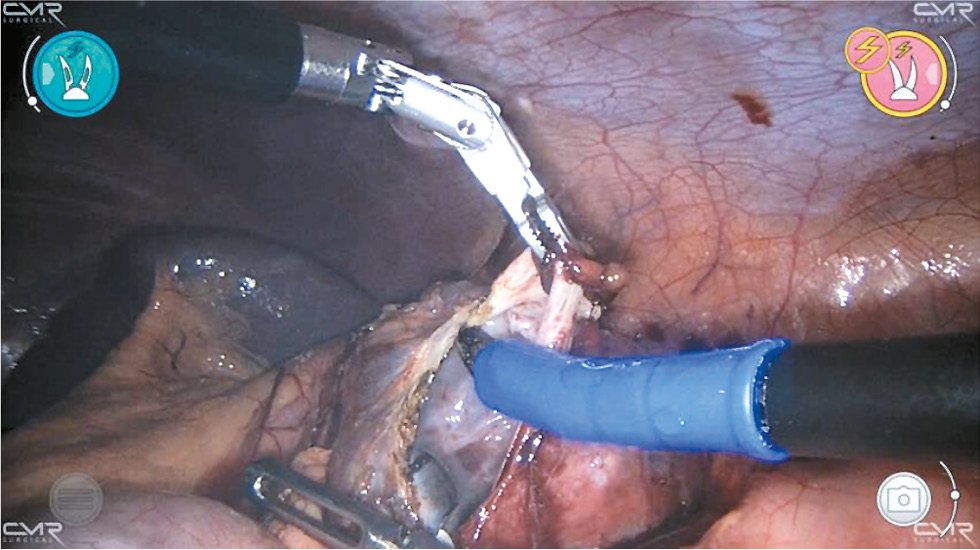

В зависимости от стороны поражения процедуру начинают с мобилизации восходящего или нисходящего отделов толстой кишки, которую затем перемещают медиально, чтобы обнажить почку. После рассечения околопочечной фасции и обнажения кисты оболочку кисты аккуратно надсекают и аспирируют жидкость. Большую часть стенки кисты, возвышающейся над тканью почки, иссекают с помощью биполярного зажима по границе аваскулярной зоны, чтобы предупредить кровотечение из почечной паренхимы, и отправляют на гистологическое исследование (рис. 2). Внутреннюю выстилку кисты подвергают аргон-плазменной коагуляции (рис. 3). В резидуальную полость устанавливают дренажную трубку, которую удаляют, когда прекращается поступление экссудата.

Рис. 3. Робот-ассистированное лечение кисты почки: этап аргон-плазменной коагуляции внутренней порции кисты.

Fig. 3. Robot-assisted treatment of renal cyst: the stage of argon-plasma coagulation of the internal portion of the cyst.